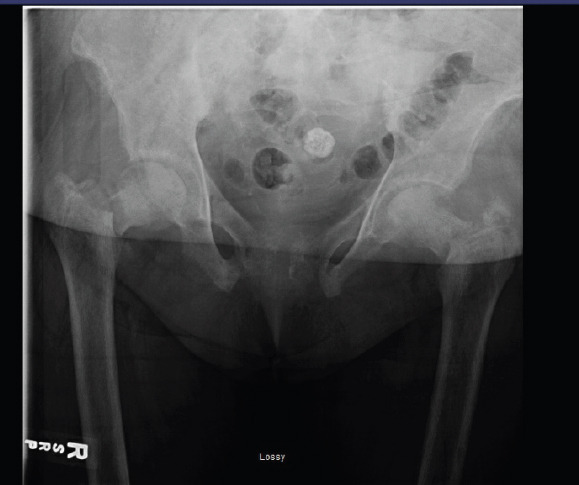

Case report: We present the case of a 50-year-old African American female with a history of ESRD on dialysis, who presented with bilateral hip pain after a minor fall. Imaging revealed bilateral displaced femoral neck fractures. Laboratory workup showed a hemoglobin level of 7.4 g/dL and microcytic anemia. Due to her chronic kidney disease, she was diagnosed with renal osteodystrophy, contributing to bone fragility. A rare Cromer blood group antibody was also detected, complicating transfusion planning. She underwent surgical repair of both hips, and her post-operative management involved coordinated multidisciplinary care addressing orthopedic, hematologic, and nephrologic concerns.